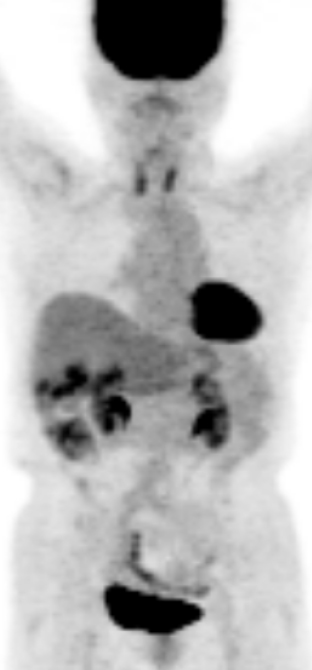

a. PET MIP像

b. PET/CT像

c. CT像、化学療法後

d. PET MIP像

e. PET/CT像

f. CT像

図2 悪性リンパ腫治療効果判定:完全寛解 化学療法前